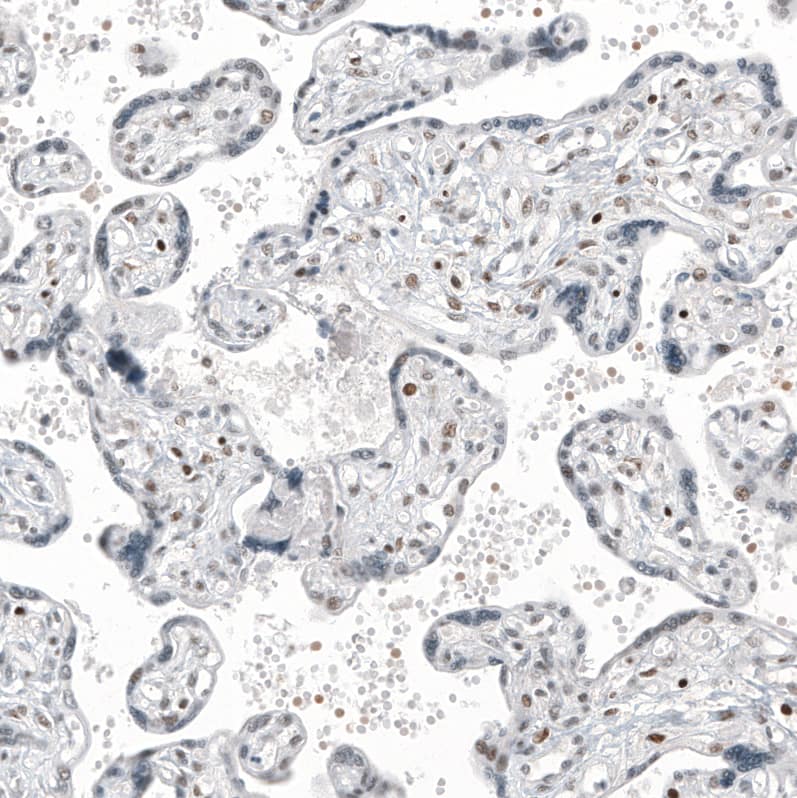

Staining of human placenta shows moderate nuclear positivity in trophoblastic cells.